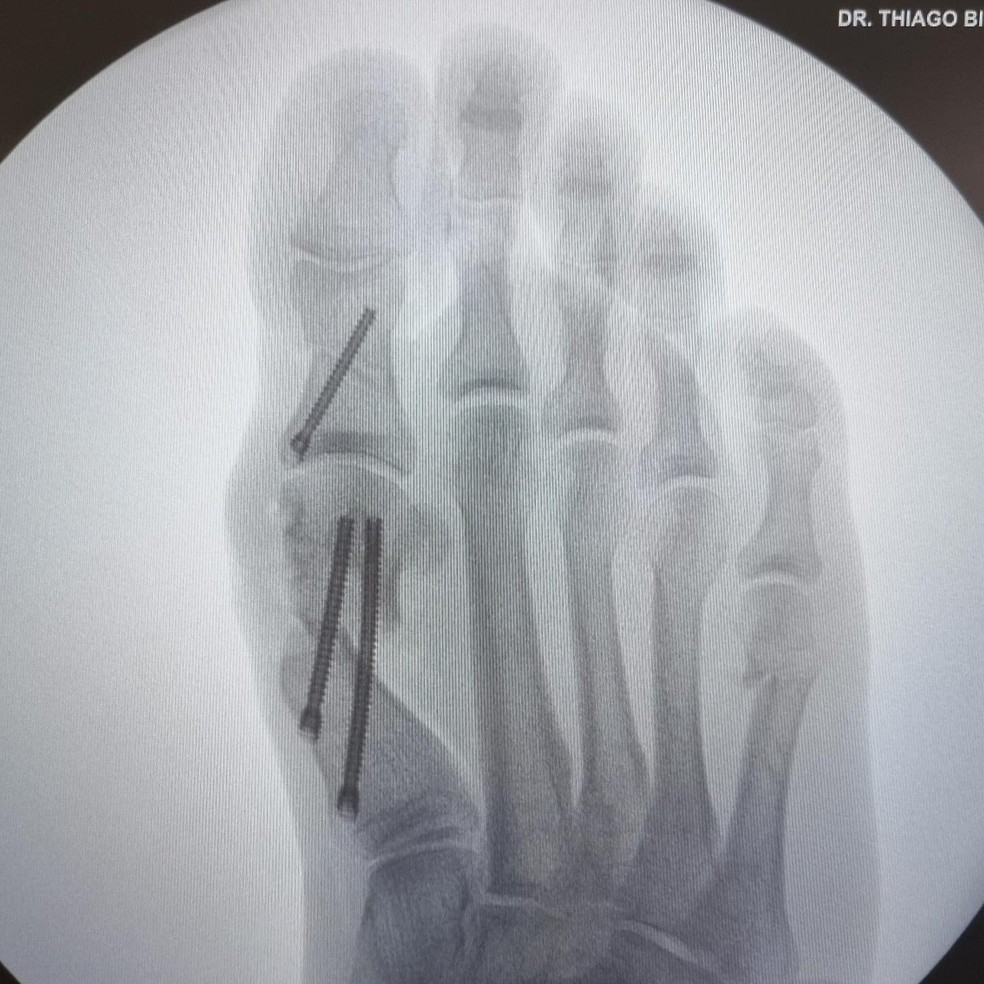

Eliezer mostra raio-x do procedimento feito no pé — Foto: Reprodução/Instagram

Ele contou que foram mais ou menos duas horas de cirurgia com anestesia local e sem cortes. O médico realiza furinhos durante o processo. Eliezer foi para a operação na última quinta-feira (26) e saiu andando.